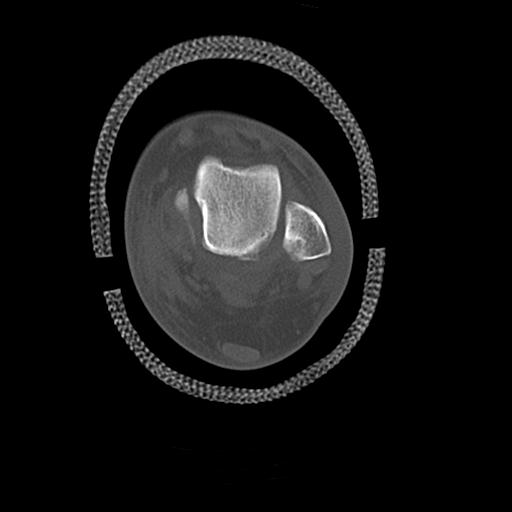

102755 1/4 2R 1/15 2R 右足関節 68歳女性 右三果脱臼骨折